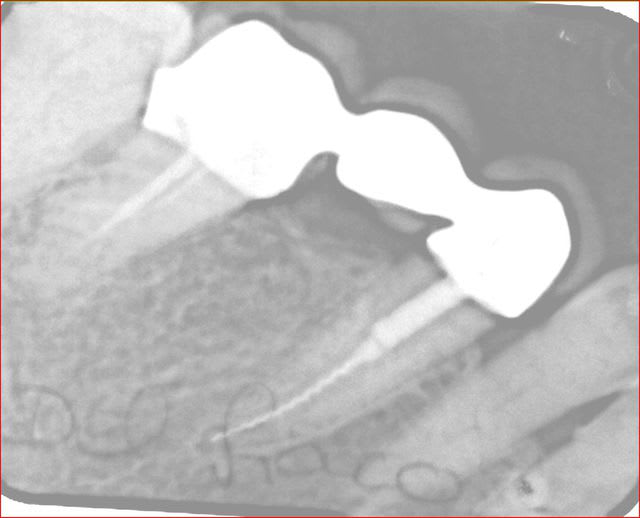

voila : depose du bridge a l arrache couronne depose de la racine coupe de la lime qui depasse amlgame a l apex repose racine et bridge dans la foulée

Avant  2  bvbppy - Eugenol

15 ans apres hlza61 - Eugenol

18/06/2014 à 18h42

C'est vrai que ça a l'air beaucoup mieux sans le bout qui dépasse...

Oui je veux bien parce que celle-là avec le gros lentulo qui reste dans la racine je trouve ça un peu couillu... Tu as fait ton obturation a retro avec quoi? Tu lui as fait directement un nouveau bridge ou tu as rescellé le vieux en contention le temps de la cicatrisation desmodontale?

l obturation a retro je l ai faite a l amalgame d argent classique . le bridge que j ai rescellé est celui d origine bien sur. je ne connais personne qui puisse faire une chir si haute sans cicatrice vestibulaire ....